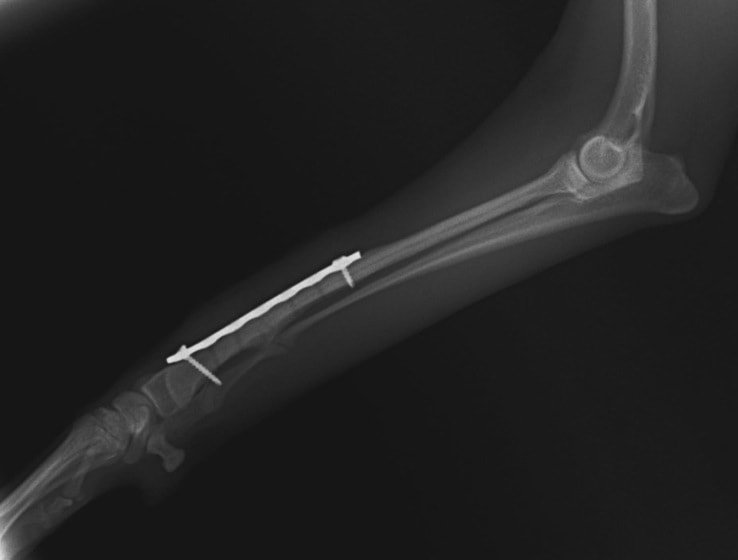

トイプードル 右遠位橈尺骨短斜骨折のALPSによる内固定

Locking Compression Plate

LCPは、スクリュー(ネジ)とプレート(金属の板)をロックする特殊な構造により骨折部位を固定する新しい世代のプレートシステムです。ひとつのホールでロッキングスクリューとスタンダードスクリューの使用を選択できるユニークな構造をしているため、骨折断端間の圧迫を目的とした従来型プレート固定法に加え、高い角度安定性を有するロッキングスクリューを用いた固定法の選択が可能です。従来のプレートシステムでは困難だった部分の骨折や癒合不全の症例に高い治療効果をもたらします。